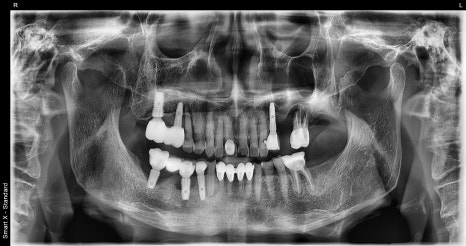

Left photo: This panoramic X-ray was taken at the patient’s first visit.

Several molars around the existing implants showed inflammation and mobility, and overall there was reduced chewing function and aesthetic discomfort.